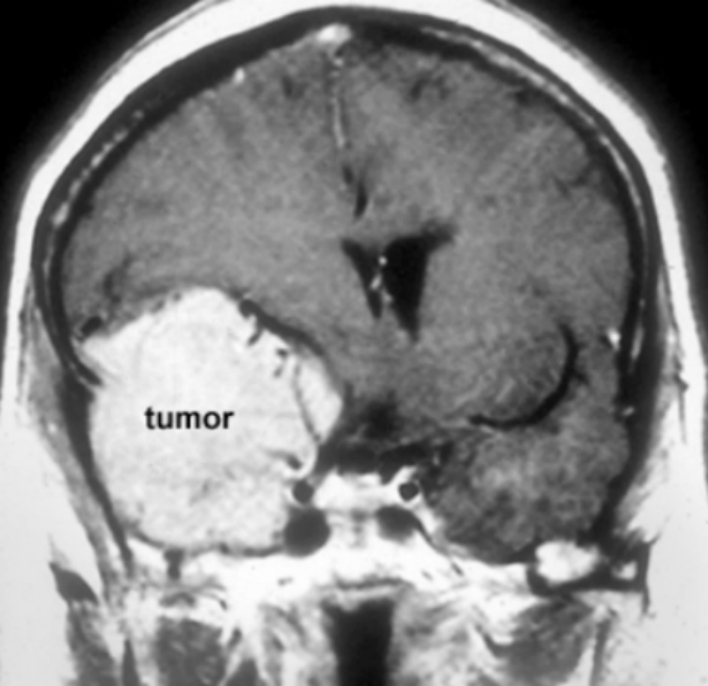

脑膜瘤3cm-4cm严重吗?脑膜瘤不开刀能活多久? 脑膜瘤(Meningiomas)是一种长在脑膜及脑膜间隙的的肿瘤,在颅内常见,80%以上脑膜瘤都是良性的肿瘤。典型的脑...

脑膜瘤 是脑膜的肿瘤,脑膜是覆盖大脑和脊髓的膜。较常见的是良性脑膜瘤或I级脑膜瘤,它们很小,不会像癌性肿瘤一样无限期地生长。非典型脑膜瘤w...

脑膜瘤是较常见的中枢神经系统肿瘤,占原发性颅内肿瘤的30%。根据国际卫生组织分类(4版)2016年修订版,脑膜瘤分为三种组织学分级和15种亚型。世卫组织...

脑膜瘤 是发生在脑膜上的脑瘤,脑膜是包围和保护大脑和脊髓的组织(图1)。尽管大多数脑膜瘤不是癌性的,但当它们生长并压迫大脑或脊髓的重要部位时,...